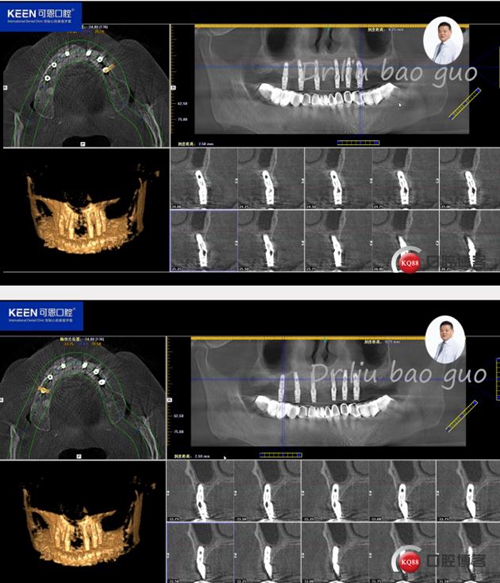

術(shù)后照片

種植后開始進(jìn)行取模,制作義齒